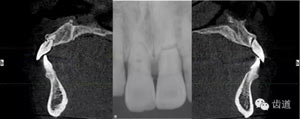

術(shù)前放射片

放射檢查:11,21根中三分之一至根尖三分之一處折斷。

術(shù)后CT